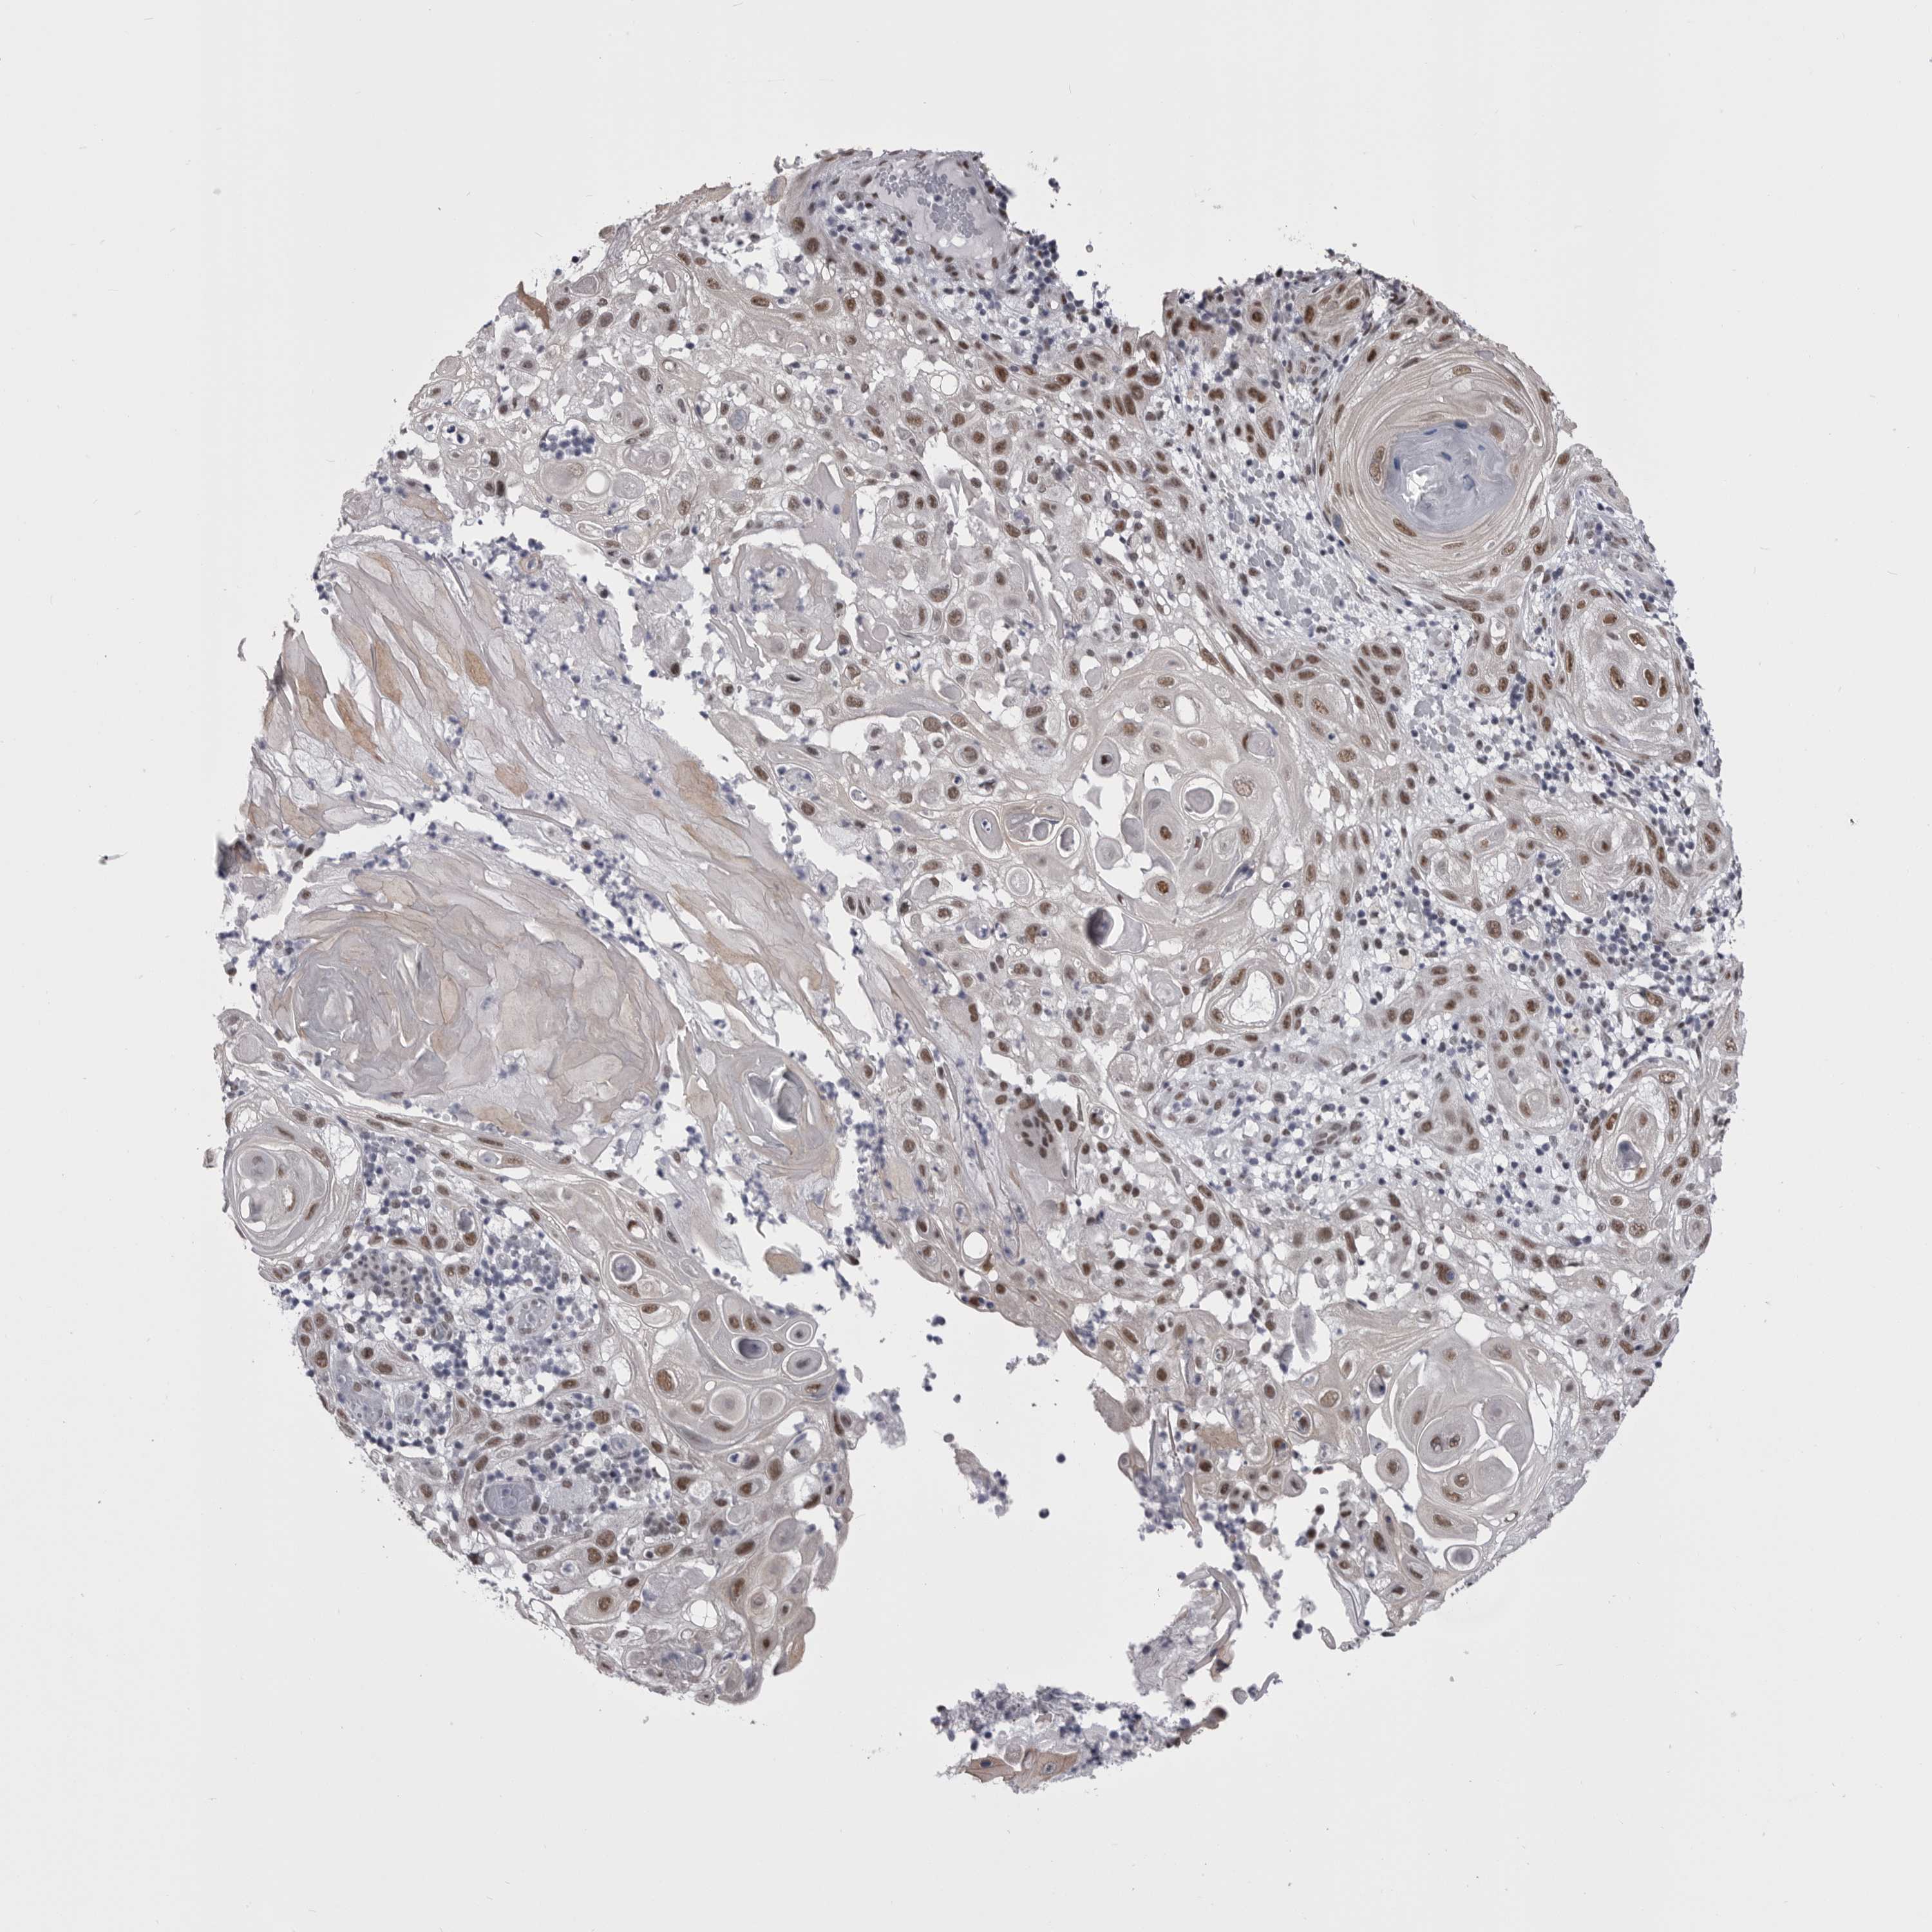

SKIN CANCER - Protein expressioni

A mouse-over function shows sample information and annotation data. Click on an image to view it in a full screen mode. Samples can be filtered based on level of antibody staining by selecting one or several of the following categories: high, medium, low and not detected. The assay and annotation is described here.

Antibody stainingi

Antibody staining in the annotated cell types in the current human tissue is reported as not detected, low, medium, or high, based on conventional immunohistochemistry profiling in selected tissues. This score is based on the combination of the staining intensity and fraction of stained cells.

Each image is clickable and will lead to virtual microscopy that enables deeper exploration of all samples and also displays staining intensity scores, fraction scores and subcellular localization as well as patient and tissue information for each sample.

Antibody HPA051587

Antibody CAB026384

Staining

High

Medium

Low

Not detected

Intensity

Strong

Moderate

Weak

Negative

Quantity

>75%

75%-25%

<25%

None

Location

Nuclear

Cytoplasmic/membranous

Cytoplasmic/membranous,nuclear

Squamous cell carcinoma, NOS